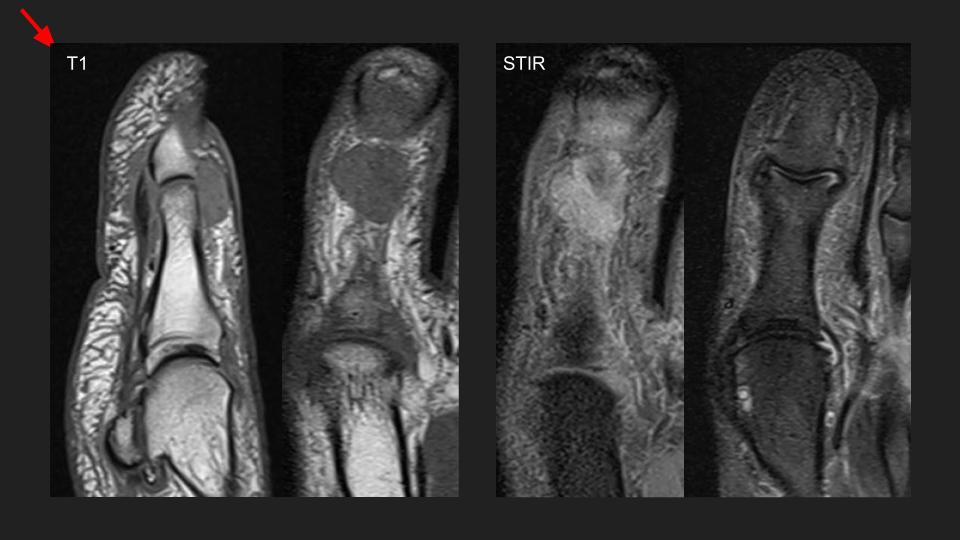

Aspirated and proven Gout of the first toe interphalangeal joint.

There is an intermediate T1 / Bright PDFS, STIR signal mass dorsal to the hallux IP with subtle erosion (arrow in short axis MRI) and no BME. No joint space narrowing, mild IPJ synovitis (not shown). XRs and US send as screenshots from referrer. She aspirated whitish greenish material from the dorsal IPJ mass/collection.